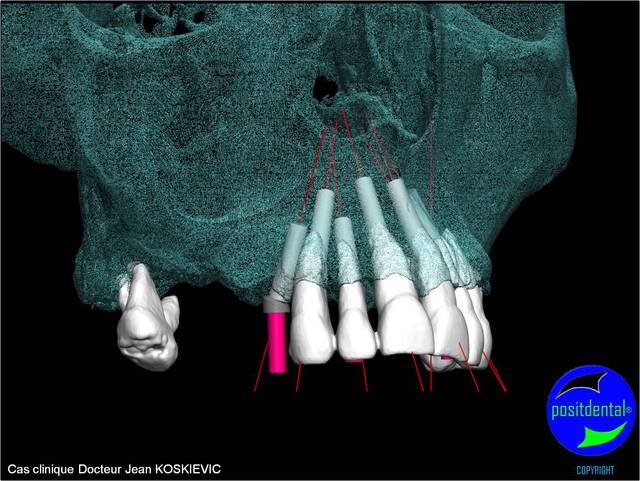

Béotien, le guide chirurgical est dispositif médical sur mesure, c’est la raison pour la quelle j’ai choisi de le concevoir et réalisé en acier chirurgical, il peut ainsi être stérilisé pour correspondre aux recommandations de la HAS (haute autorité de santé), son design et étudié pour facilité l’irrigation externe, les outils connexe soit standard soit développés spécifiquement par Positdental ont le marquage CE et ma qualité de prothésiste dentaire m’autorise à remplir le certificat de conformité répondant aux exigences relative à directive européenne n° 93/42 CEE. Pour la deuxième question une formation clinique et théorique par des praticiens sous l’égide du Docteur Jean KOSKIEVIC et technique ainsi que des cas cliniques accompagnés se met en place. En effet l’implantation bi maxillaire est complexe et demande beaucoup d’attention.

rendu 3D maxillaire sup, pano et photo

Mci - Eugenol